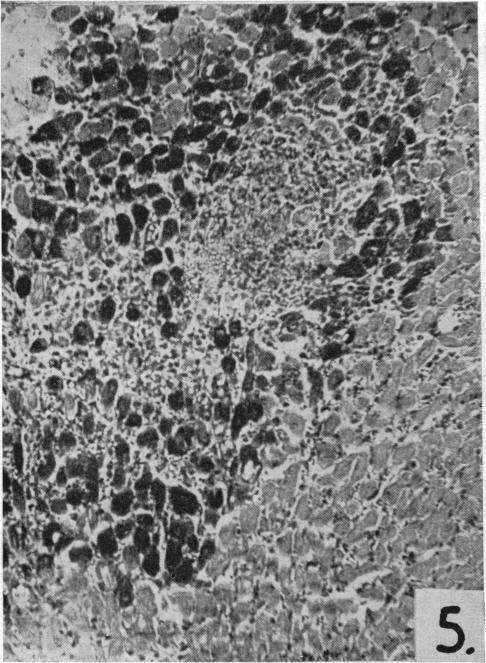

Dietary choline and the maintenance of the cardiovascular system in rats.

Br Med J. 1954 Jul 3;2(4878):1-5. doi: 10.1136/bmj.2.4878.1.